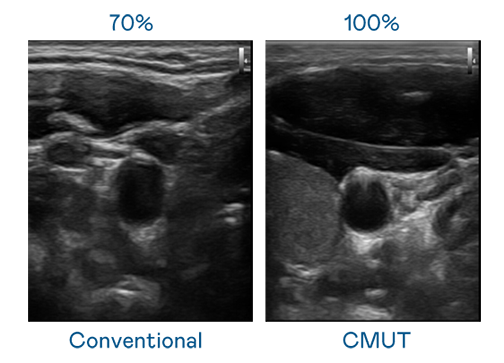

CMUT 技术是一种用电容式微机电元件来产生超音波讯号的技术。与传统 PZT 压电式技术相比,CMUT 频宽增加 30%,更宽频的超音波讯号让影像解析度大幅提升,是实现高影像品质医疗超音波扫描、促进精准医疗发展的关键技术。

超音波影像的解析度高低,首先取决于探头能发出的讯号频宽。PT视讯 CMUT 可提供高清晰的超音波讯号,提供高频宽、高灵敏度、影像纹理细节更高的超音波影像,协助医护人员缩短影像判读时间及利用精准的医疗影像进行诊断。